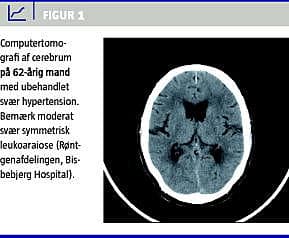

Hypertension medfører en acceleration i udviklingen af aldersinducerede forandringer i hjernens hvide substans, såkaldt leukoaraiose [2]. Disse forandringer kan ses på computertomografi (CT) og magnetiske resonans-skanninger (Figur 1 og Figur 2 ). Forandringerne er af iskæmisk natur og skyldes hypoperfusion i mindre kar, der medfører en udtynding af vævet. Hjernen er yderst følsom for øgning i blodtryksniveauet, og selv få mmHg's øgning i blodtryksniveauet i en døgnblodtryksmåling kan relateres til øget forekomst af hvid substansforandringer og øget hjerneatrofi efter bare få års observationstid [3]. Ud over alder og hypertension bidrager lakunære infarkter, rygning og hyperkolestrolæmi til udvikling af hvid substans-forandringer, idet disse faktorer også fører til iskæmisk cerebrovaskulær sygdom. Personer med hvid substans-forandringer har en øget risiko både for at få apopleksi og udvikle demens.